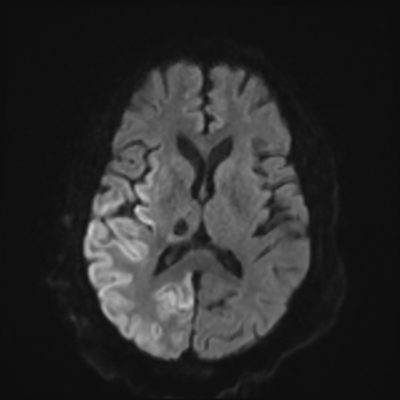

You come back the next day and see how things are going. The patient's electrographic record has shown a moderate encephalopathy (diffuse slowing, disorganization) with frequent right posterior quadrant delta slowing. Based on this result, and an adequately improved clinical examination, you give the okay to proceed with obtaining an MRI of his brain. This is shown below.

MRI brain (DWI)